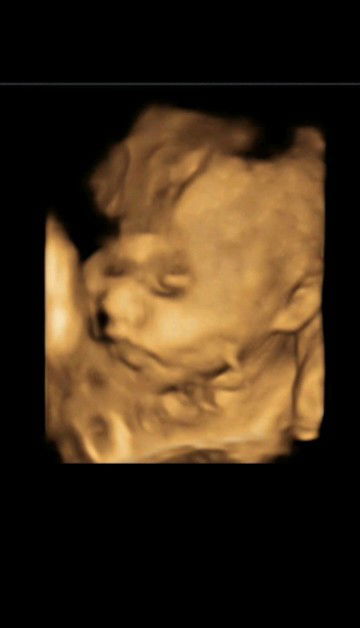

Hari ini saya jatuh terpeleset posisi saya menekan perut apakah akan terjadi sesuatu pada janin saya